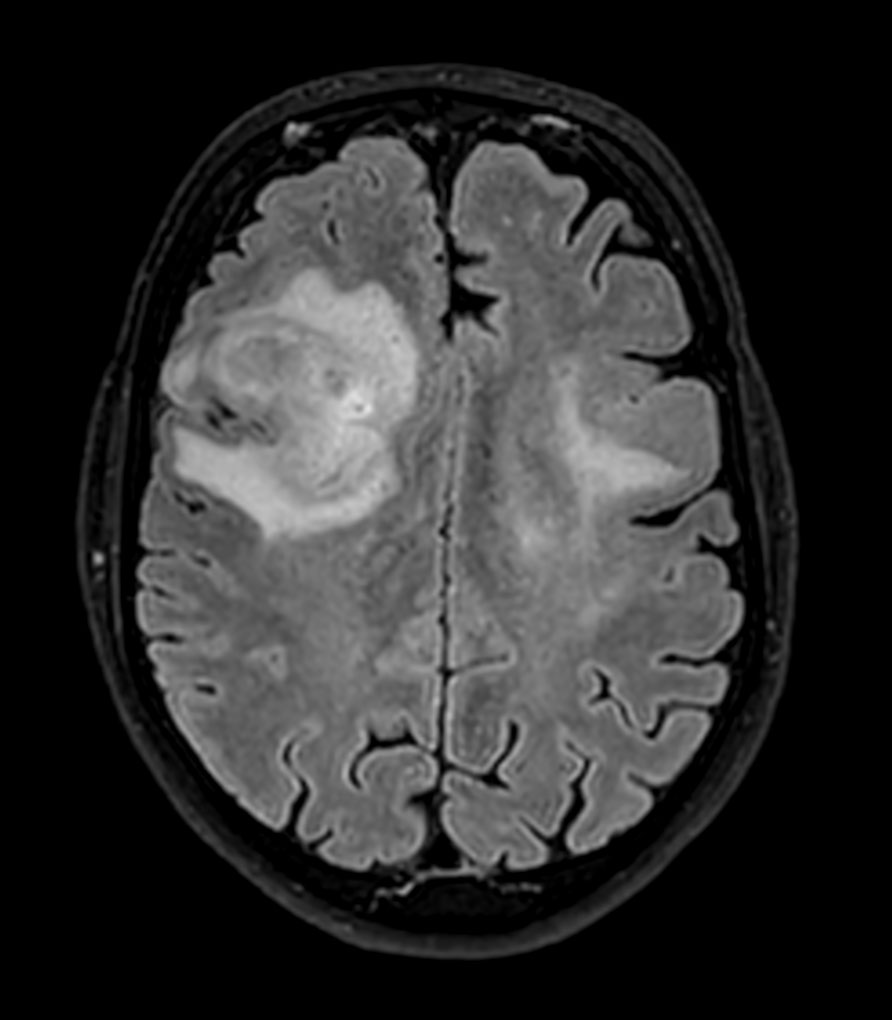

Axial 3D BrainVIEW FLAIR